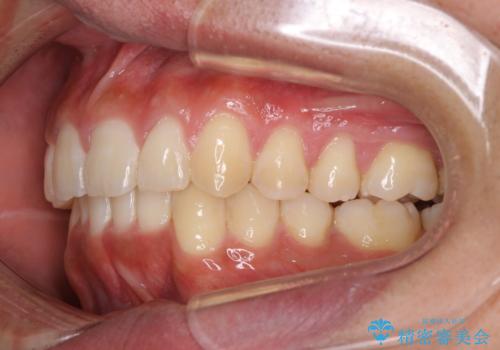

インビザラインによる出っ歯の矯正

- 出っ歯と下の歯のガタガタを主訴に来院されました。

上の奥歯を後方に移動させて、スペースを作り前歯を内側に引っ込める計画としました。

インビザラインによるマウスピース矯正で治療をすることとしました。

インビザラインをしっかり使用していただいたので、スムーズに治療をおえることができました。